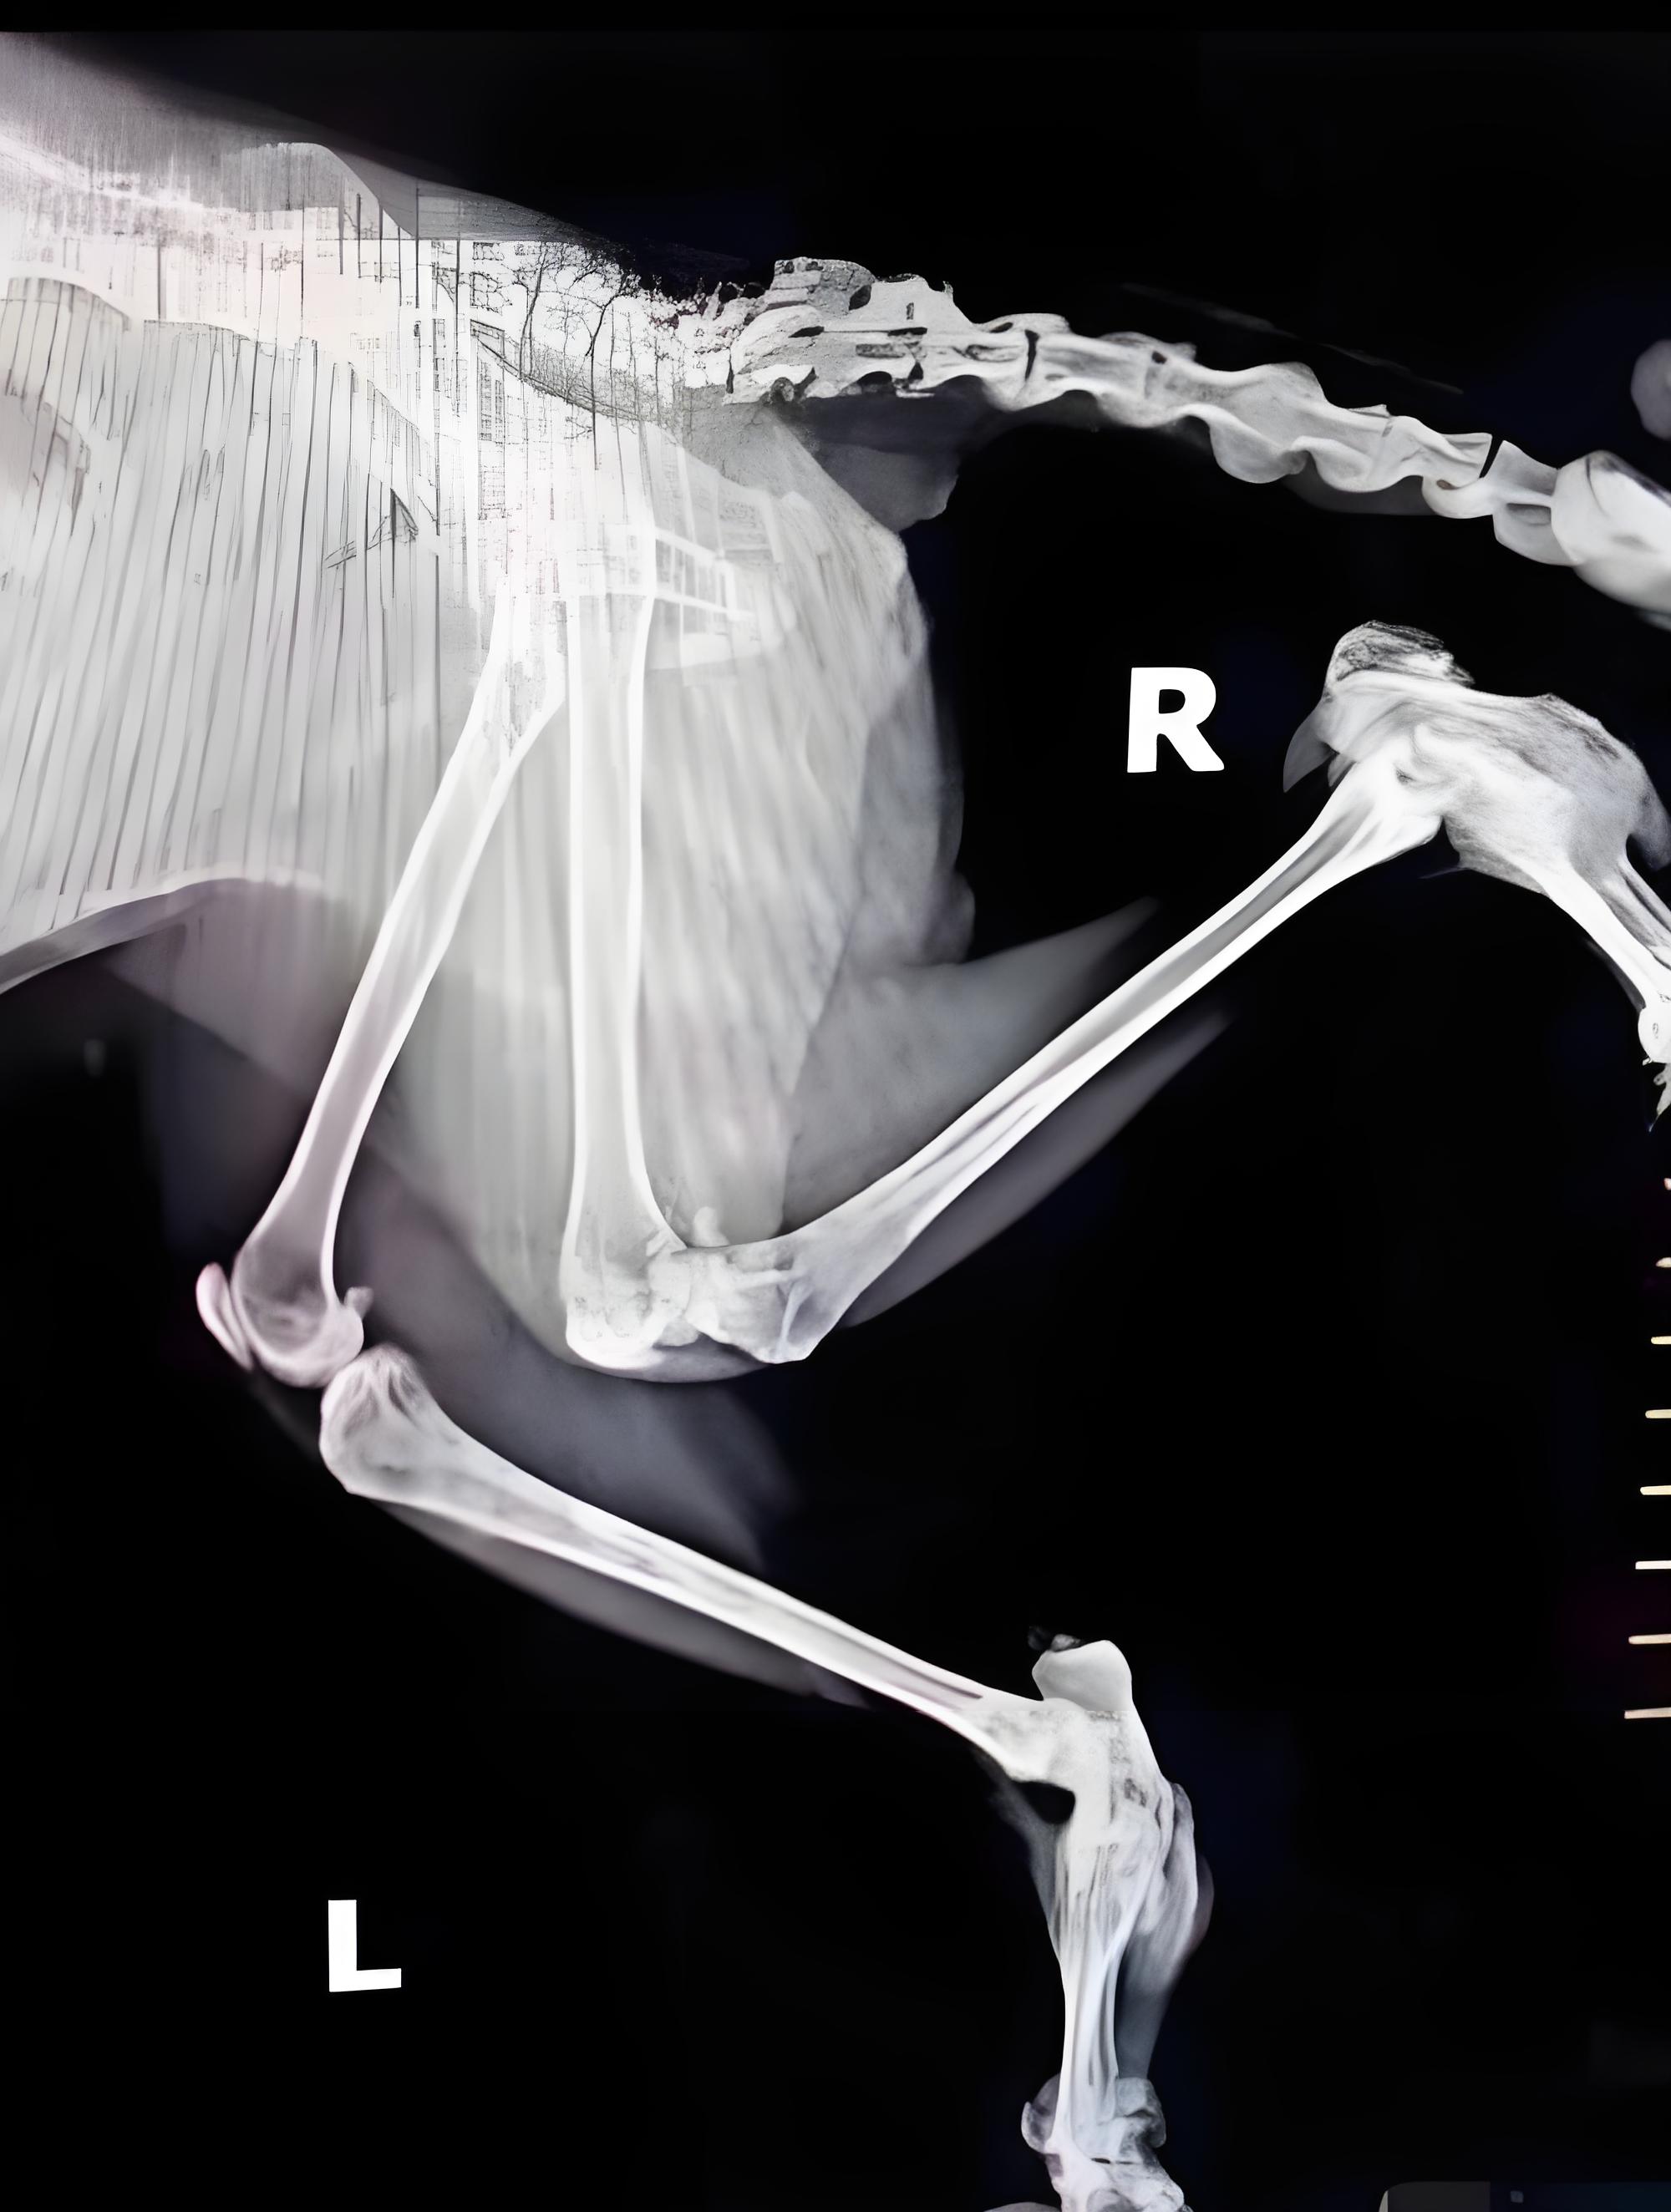

Diagnostic Approach:‌

Radiographic examination (X-ray) for calcified cartilage flaps